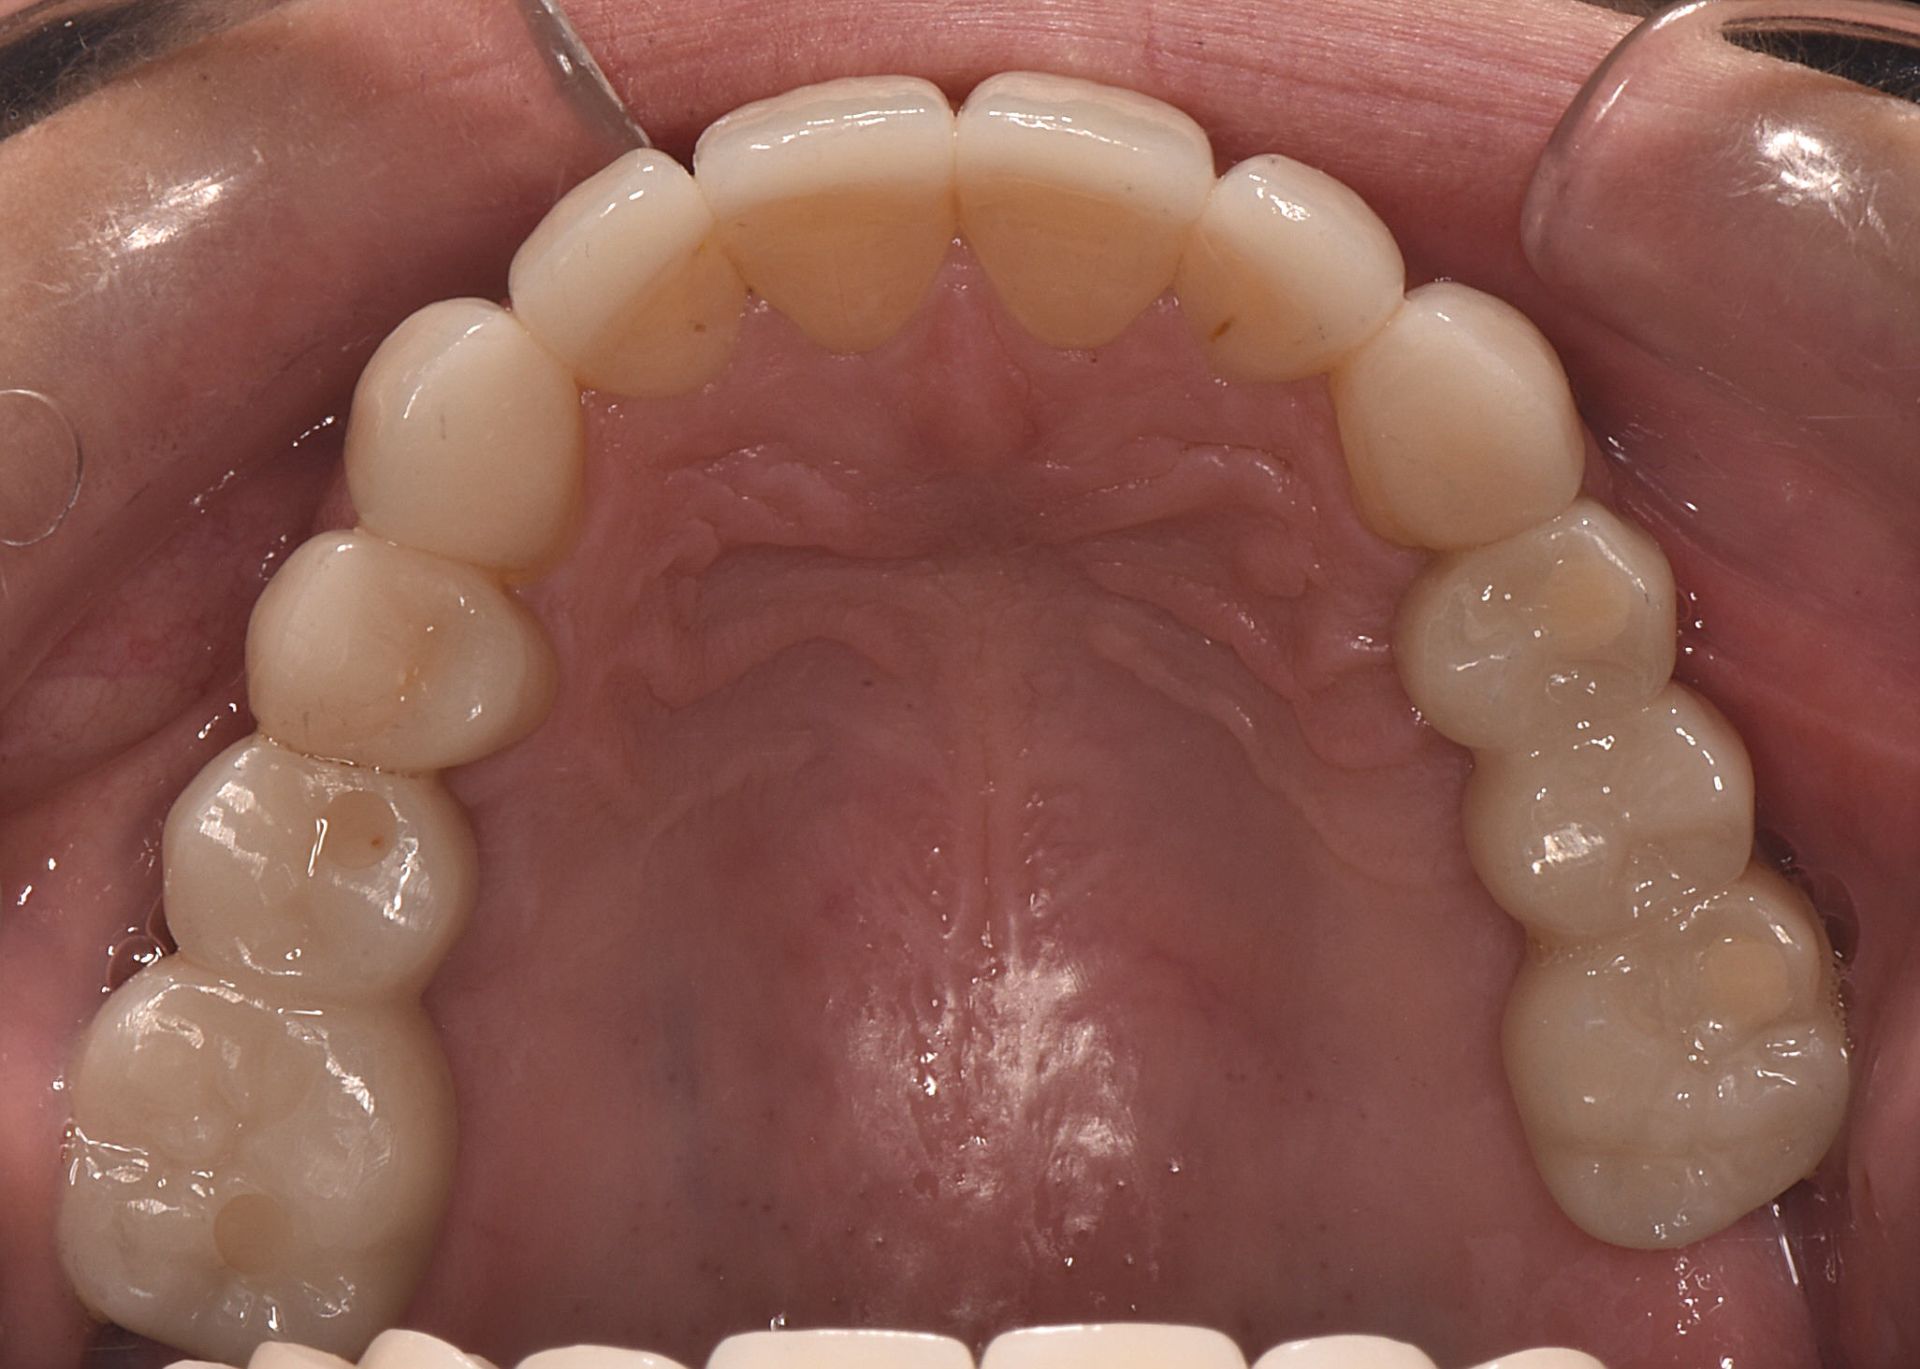

Zirconia bridge on Southern DC Implants

Tooth Replacement